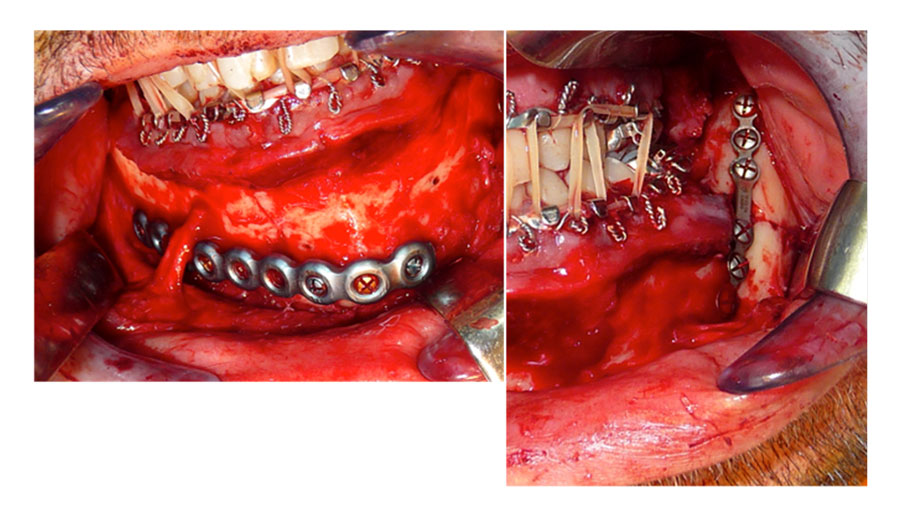

I agree, you have to have that constant back and forth between occlusion and seeing what the fractures are doing. And it's really that the big picture view that you have to keep in mind. So, you've got them into a good occlusion and these are the plates that you chose to use.

Maybe you can just briefly explain why you decided on this inferior border plate for the parasymphyseal fracture and the Champy plate for the angle fracture.

Dr. Susarla: It kind of goes back to what we were talking about earlier, is that when you have bilateral fractures at the mandible, one approach that I think works really well is to simplify the injury by putting true rigid fixation on one site so that you have a little more flexibility with the other site. In this case, we used an intraoral approach as you can see, you can see the mental nerve dissected completely free.

And then we used a heavy locking reconstruction plate for the parasymphyseal fracture with three bicortical screws on either side. The key advantage of this is this is true rigid fixation for this region of the mandible. You can essentially have the patient without an arch bar at the end of the case. If you were to use a lighter plate that didn't meet the requirements for true rigid fixation and isolation, then you might have to consider leaving a tension band on

Which would be hard in this case to put a mini plate above this because of the location of the mental nerve. And then you might be obligated to leave the arch bar on, which presents its own challenges with hygiene and using or having true rigid fixation in a parasymphyseal fracture then gives you a little more flexibility with the angle.

So as you mentioned, when we expose the angle, if you're able to get it into a good anatomic alignment with visual inspection at the superior border and either a direct inspection from an intraoral approach for the inferior border or just by palpation, you might be able to use something that would be functionally stable fixation or semi-rigid fixation, which in this case is this Champy miniplate.

Dr. Hopper: In September we'll be talking about favorable and unfavorable angle fractures and a number of plates and association between infection and a number of plates. But for this webinar, just for the watchers, that you have two approaches to that parasymphyseal fracture. One is the skeletonization of the nerve, like Dr. Susarla has done here.

That gives you a beautiful view of the inferior border. You have to be very technically meticulous to be able to do that. And it also makes it possible to get direct visualization of your screw fixation posteriorly behind the fracture. If you don't skeletonize the nerve, you can skirt underneath the nerve, but like Dr. Susarla had mentioned earlier, it gives you a very limited view of that posterior plate.

And you have to be very careful that you're not running off the inferior border. And in some cases, you have to go percutaneous to get those posterior screws in because you don't have adequate exposure. Both are very reasonable approaches and both of us do both of them from time to time, depending on the case. But just to let you know, you don't always have to skeletonize the nerve in this case.